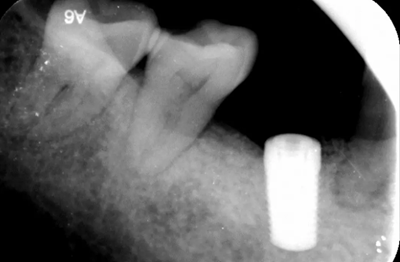

植骨術(shù)后半年根尖片,種植體周圍愈合較好遠(yuǎn)中少量骨吸收。

(攝于2018年4月20日)